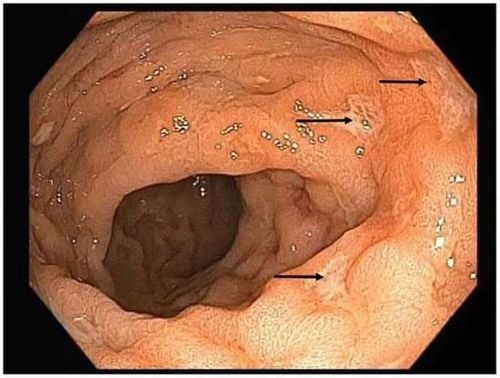

• Nội soi trực tràng hoặc nội soi đại tràng: Kiểm tra ống hậu môn và phần dưới trực tràng hoặc toàn bộ đại tràng bằng ống nội soi mềm. Trong trường hợp chỉ nội soi trực tràng, bệnh nhân không cần phải nhịn ăn hoặc xổ ruột trước đó.

Viêm trực tràng là tình trạng lớp niêm mạc của trực tràng bị viêm, làm bệnh nhân thấy khó chịu hoặc đau đớn và trong một số trường hợp có thể gây chảy máu hoặc tiết dịch nhầy từ trực tràng. Viêm niêm mạc trực tràng có thể xảy ra trong thời gian ngắn hoặc trở thành bệnh mãn tính.